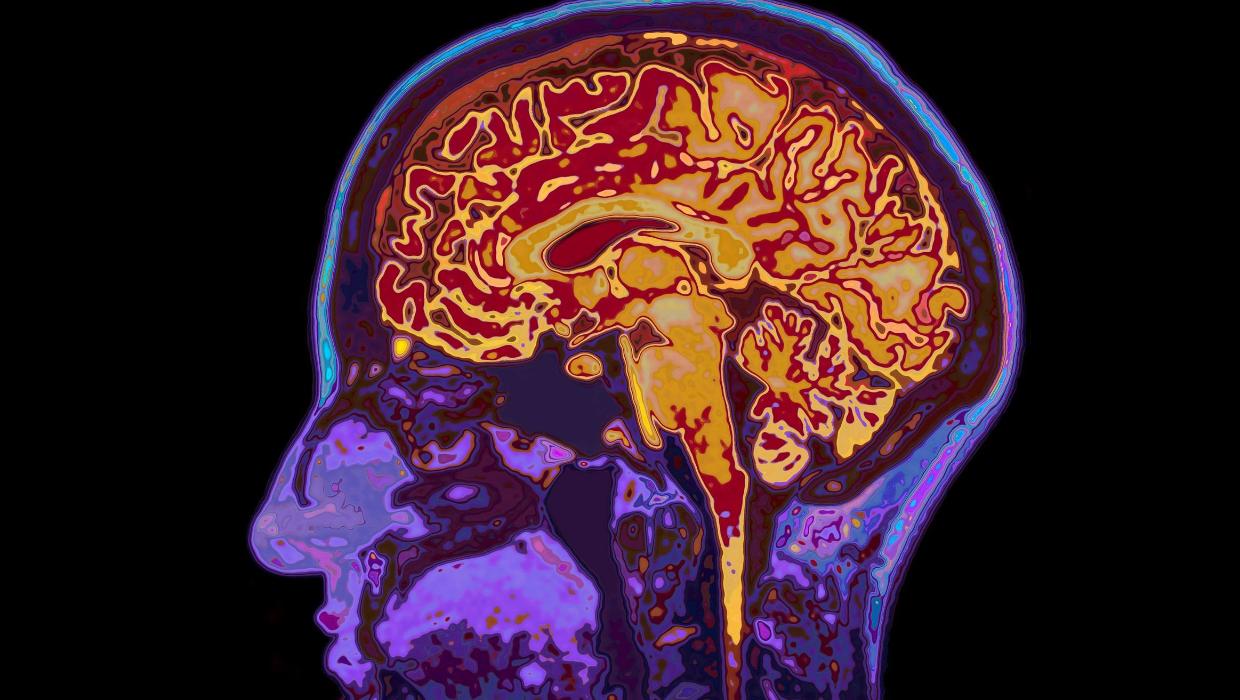

A recent study conducted by the **University of Cambridge** reveals significant findings regarding the stages of brain development. The research indicates that human brains remain in a state of adolescence until the age of **32**, while the onset of aging begins at **66**. This groundbreaking study outlines five major epochs of brain development, highlighting key turning points that occur throughout a person’s life.

The research, published in **March 2024**, identifies four critical transitions in brain maturation. These transitions mark the progression from childhood through adulthood and into older age, providing a clearer understanding of how brain function evolves over time. The findings suggest that the brain undergoes substantial changes well into early adulthood, a period often characterized by ongoing emotional and cognitive development.

Additionally, the research highlights the implications of aging on cognitive abilities. As individuals reach the age of **66**, the brain begins to exhibit signs of decline in certain functions, which can affect memory and decision-making processes. This age-related change underscores the need for continued support and intervention strategies aimed at promoting cognitive health in older adults.

In conclusion, the **University of Cambridge** study provides valuable insights into the human brain’s evolution throughout life. Recognizing that brain development persists until **32** and that aging begins at **66** opens avenues for further investigation into how these factors influence behavior, learning, and overall well-being. As society continues to grapple with the challenges of aging populations, understanding these developmental stages will be essential in promoting healthier, more informed living.